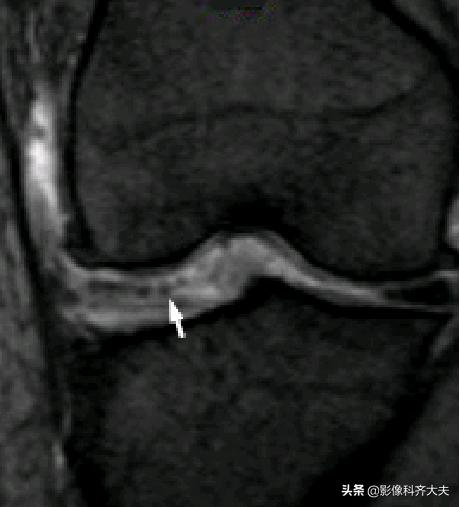

容易误诊为半月板损伤的正常解剖结构

后股板韧带: